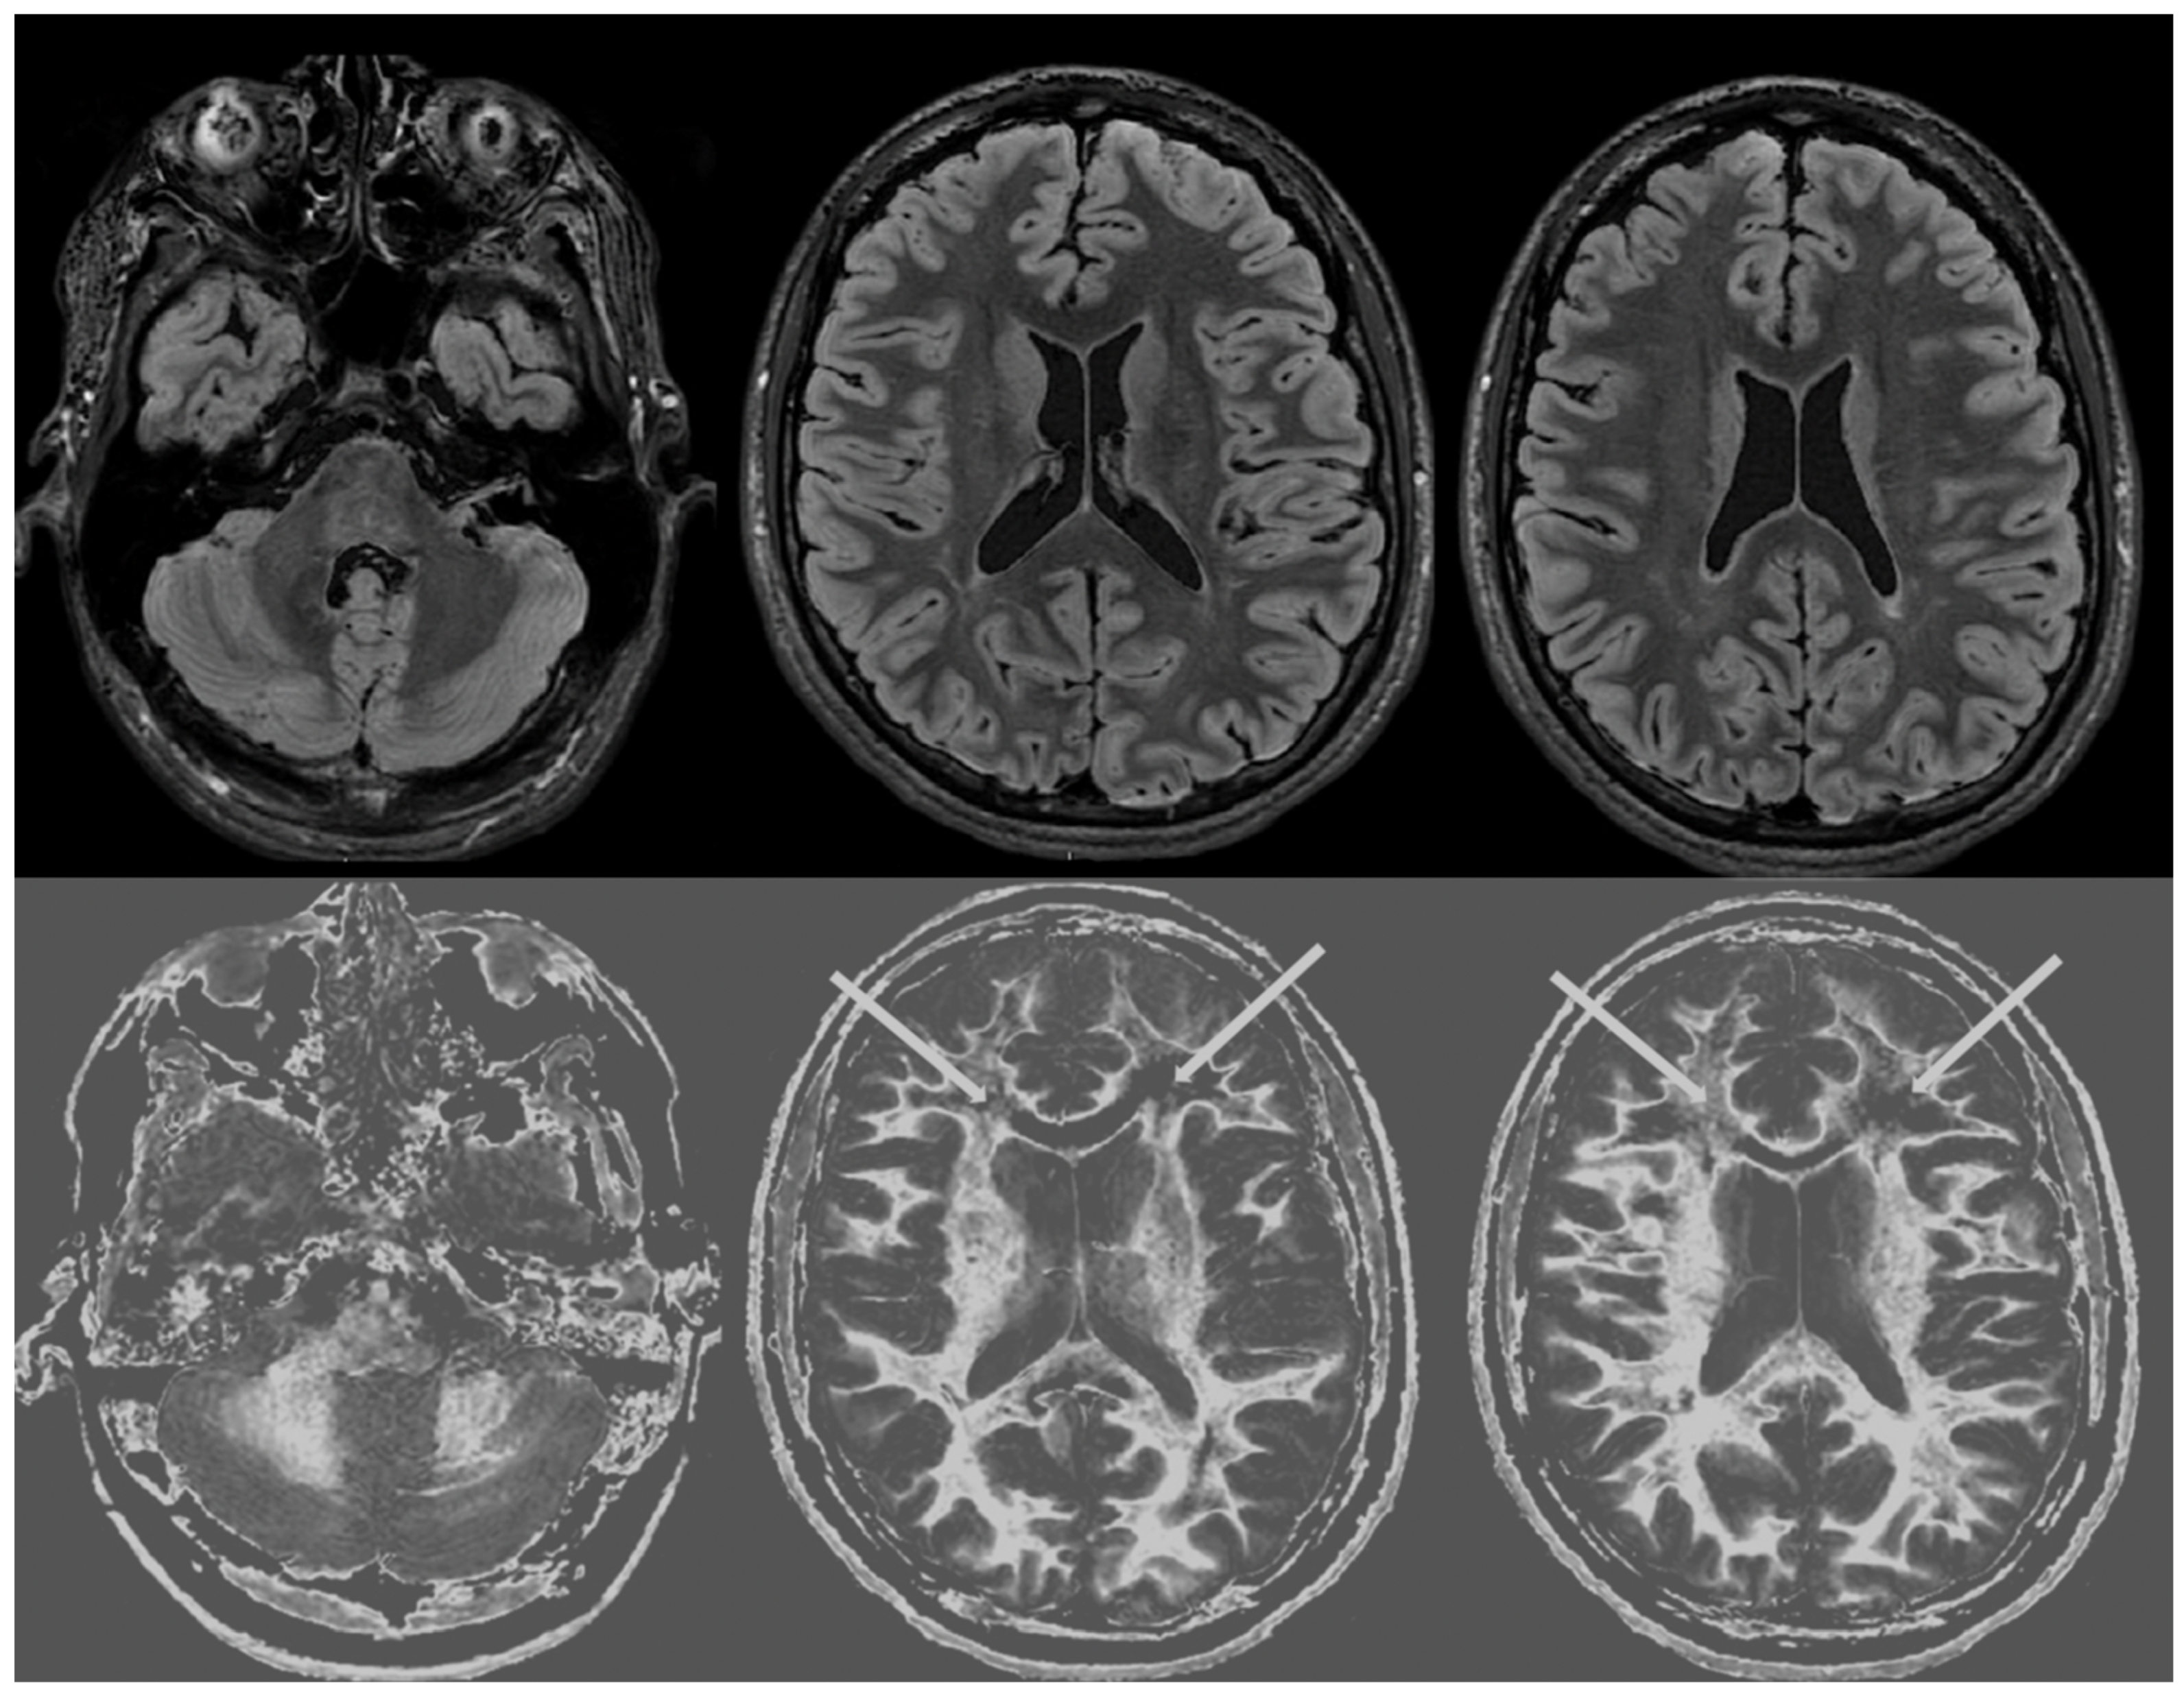

Figure 4 and Figure 5 show T2-FLAIR images (upper rows) with positionally matched dSIR images (lower rows). No abnormality is seen in white matter on the T2-FLAIR images, but very extensive high signal abnormalities are seen in white matter on the corresponding dSIR images. In Figure 4, there is sparing of white matter in the anterior central corpus callosum and adjacent forceps minor, which have a dark appearance (long white arrows). There is also some sparing of the posterior central corpus callosum. In Figure 5, there is sparing of the peripheral white matter of the cerebral hemispheres, which have a dark appearance (long white arrows). Small focal lesions of a relatively increased signal are also seen in the white matter in Figure 5 (grey arrows) on the dSIR images. High signal boundaries between the white and grey matter are seen, but these are less obvious in many areas because of the high signal present in much of the white matter.

Overall, the abnormalities are bilateral and symmetrical and involve most of the white matter of both the cerebral and cerebellar hemispheres. The appearances in the patient are strikingly different from those in the normal control shown in Figure 3, where normal white matter has a low signal (dark appearance), apart from the corticospinal tracts and areas adjacent to them, which are mid-grey.

Figure 4. Case 1 was examined nine months after a severe drug overdose. Comparison of positionally matched T2-FLAIR images (upper row) and narrow mD dSIR images (lower row). No abnormality is seen on the T2-FLAIR image, but there are extensive areas of a high signal in the white matter of the brain. Only the anterior and posterior central corpus callosum and parts of the frontal lobes have a low signal (dark appearance) and look normal on the dSIR images (white arrows) (lower row). High signal boundaries are seen at the junction between the white matter and grey matter but are rendered less obvious in many areas because of the high signal in much of the white matter.

Figure 5. Case 1 was examined nine months after a severe drug overdose. Comparison of positionally matched T2-FLAIR images (upper row) and narrow mD dSIR images (lower row) (higher cerebral hemispheres). No abnormality is seen on the T2-FLAIR images, but there are extensive areas of high signals in the central white matter of the brain (lower row). Only some of the peripheral white matter on the lower images appears dark and looks normal on the dSIR images (white arrows) (lower row). Some other areas of white matter have a mid-grey appearance consistent with a lesser degree of abnormality. Small focal lesions are also seen on the dSIR images (grey arrows) but not on the T2-FLAIR images.